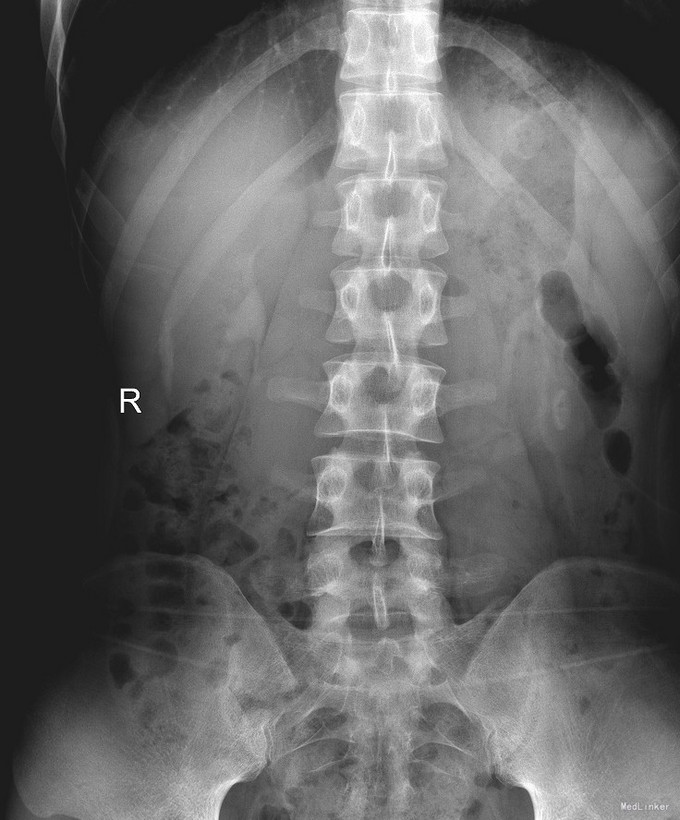

椎管侧隐窝占位1例

左侧下肢放射痛1月加重2天

腰椎前屈受限,腰4-5左侧棘突旁压痛,左侧直腿抬高试验小于30°,肌力正常。

腰椎椎管内占位 腰椎后路开窗减压+椎间融合+内固定术